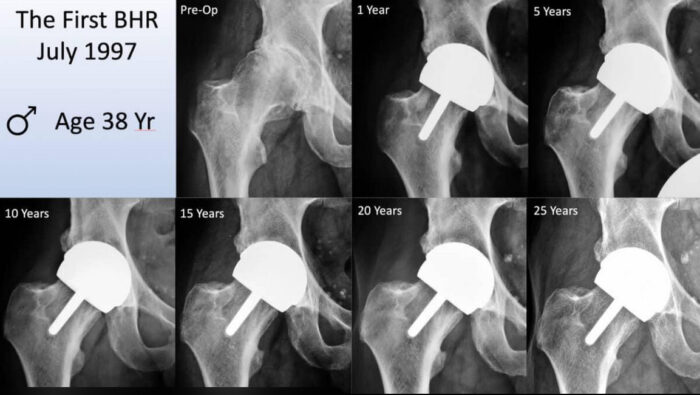

First BHR x-ray from 1997 up to 25 years

👉 The breakthrough moment:

• July 30, 1997 – the first modern

Birmingham Hip Resurfacing was implanted

💬 Why this mattered:

“This marked the beginning of modern hip resurfacing.”